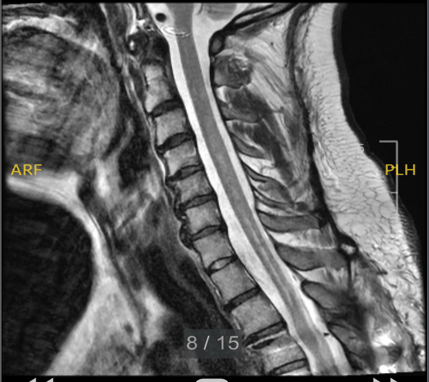

Diagnosis of syrinx is guaranteed through MRI. Using an instrument such as MRI, healthcare professionals can assess the size, location (cervical syrinx, thoracic syrinx, or other), and associated abnormalities, such as Chiari malformation or spinal cord tethering. Once detected, MRI is used serially to document progression.